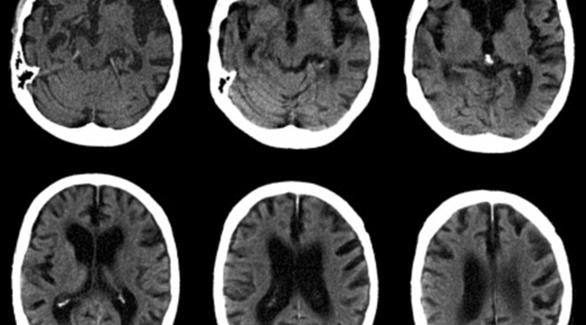

ربط باحثون من جامعة بوسطن الأمريكية بين ارتفاع نسبة الإجهاد بزيادة خطر الإصابة بالزهايمر معتبرين أن إفراز المزيد من هرمونات الإجهاد يؤدي إلى إنتاج كميات من البروتينات تسمى بمركب "تاو" بطريقة غير طبيعية.

وأفادت صحيفة دايلي ميل البريطانية أن مركب تاو الخاص بالتوتر يعيش فترة قصيرة ولكن في حالة التوتر المزمن أو طويل الأجل، يتكون تاو باستمرار ليشكل مجموعات، وهذه المجموعات تؤدي إلى ضمور الخلايا العصبية.

وأفاد الباحثون أن الإجهاد المزمن والهورمونات التي تترافق معه يمكن أن تسرع تطور مرض الزهايمر.